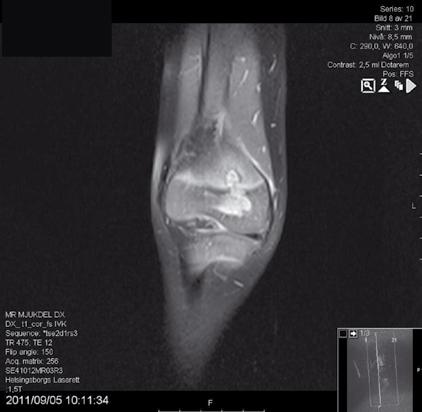

Med tredimensionell gånganalys registreras rörelsemönstret, och den kraftutveckling som de olika muskelgrupperna genererar under gångcykeln beräknas i tre plan (sidoplan, frontalplan och rotationsplan). Muskler som arbetar med förkortning (koncentriskt) bidrar till att vi rör oss framåt verkar framförallt i sidoplanet. Magnetkameraundersökning används för att mäta muskelvolym och benlängd. Självkänsla mäts med det validerade självrapporterande frågeformuläret ”Jag tycker jag är”. Känsla av sammanhang (KASAM) mäter självbilden och EQ-5D är en kort enkät som värderar livskvalitet.

Bäckenhöjd, femuroch tibialängd liksom talus- och calcaneushöjd mäts på magnetkamerabilder.